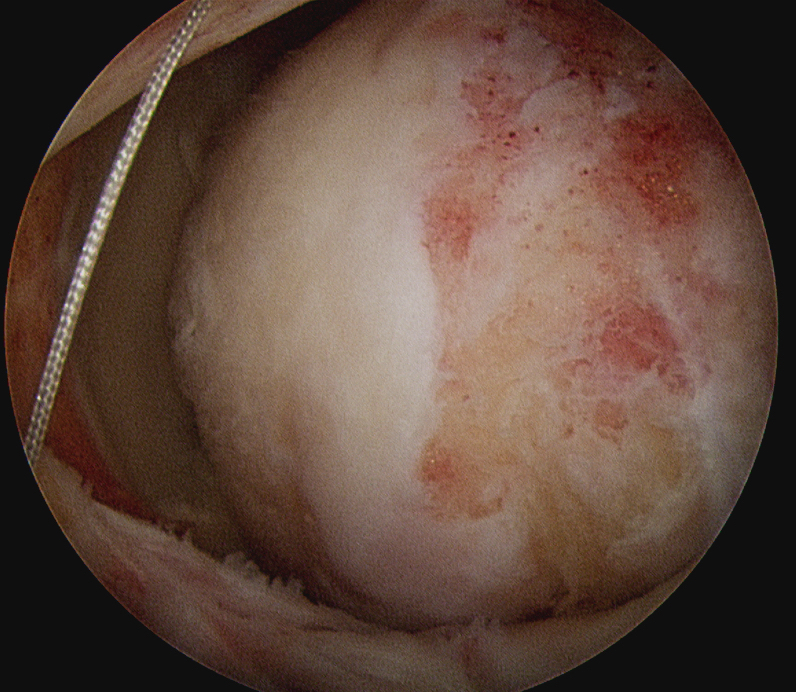

Static stabilizer

- between glenoid and greater tuberosity of humerus

- restrict superior migration of humeral head

Subacromial arthroscopy

- prepare superior surface of glenoid and greater tuberosity

- measure defect size with arm in 30 degrees abduction and 15 degrees external rotation